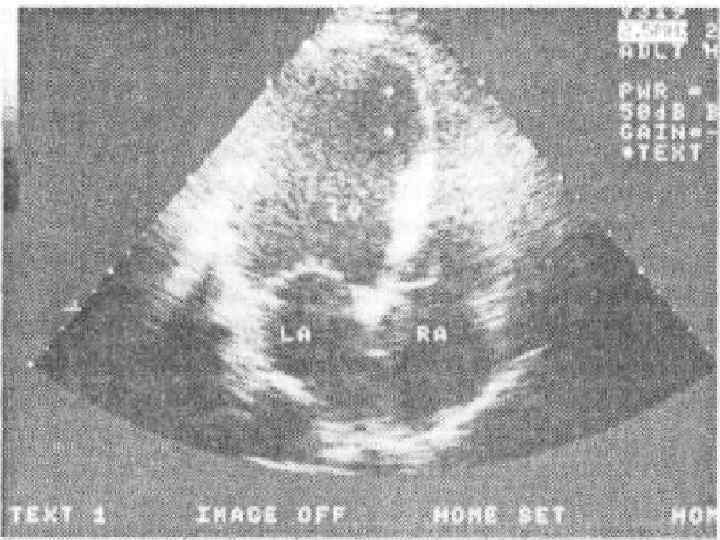

Ультразвуковая анатомия сердца В эхокардиографии используют ряд доступов к сердцу и магистральным сосудам: • Левый парастернальный • Апикальный • Субкостальный • Супрастернальный • Правый парастернальный

ОЦЕНКА НАРУШЕНИЙ РЕГИОНАЛЬНОЙ СОКРАТИМОСТИ ЛЕВОГО ЖЕЛУДОЧКА Выявление локальных нарушений сократимости ЛЖ с помощью двухмерной эхокардиографии имеет важное значение для диагностики ИБС. Исследование обычно проводится из верхушечного доступа по длинной оси в проекции двух и четырехкамерного сердца, а также из ле вого парастернального доступа подлинной и короткой осям. В соответствии с рекомендациями Американской ассоциации эхокардиографии ЛЖ при этом условно делится на 16 сегментов, располагающихся в плоскости трех поперечных сечений сердца, зарегистрированных из левого парастернального доступа по короткой оси. Изображение 6 ти базальных сегментов — переднего (А), переднеперегородочного (AS), задне перегородочного (IS), заднего (I), заднебокового (IL) и переднебокового (AL), — получают при локации на уровне створок митрального клапана (SAX MV), а средних частей тех же 6 ти сегмен тов — на уровне тапиллярных мышц (SAX PL). Изображения 4 верхушечных сегментов перед него (А), перегородочного (S), заднего (I) и бокового (L), — получают при локации из парастер нальногодоступа на уровне верхушки сердца (SAX АР).